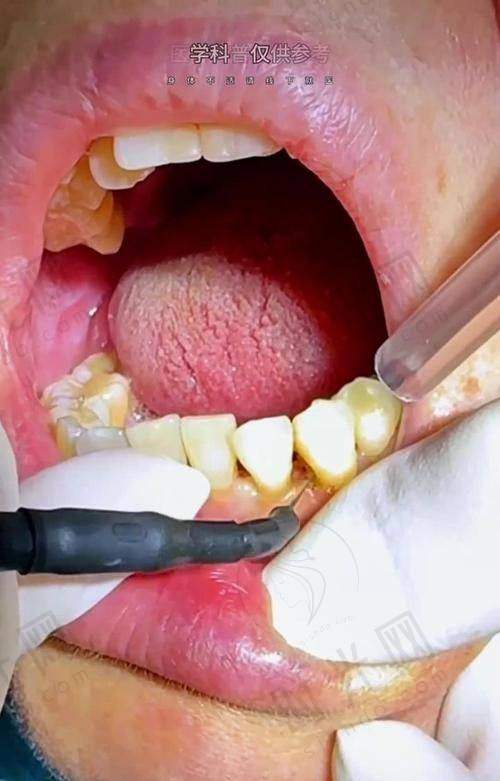

补牙拔牙及其他牙齿治疗相关费用也特别清晰。超声波洁牙180元起,能有效清洁牙齿;根管治疗580元/根起,解决牙齿疼痛问题;进口树脂补牙380 - 1080元/颗起,修复牙齿的外形和功能。